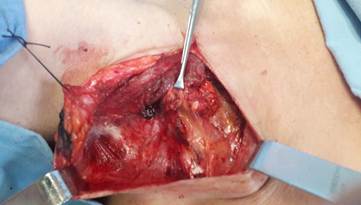

En el nódulo patológico se realizó la inyección de 0,5 a 1 ml de azul de metileno diluido en 5 a 10 ml de solución salina normal (SSN 0,9%), bajo guía ecográfica en tiempo real (Figura 2). La coloración funcionó de una manera eficaz para teñir el ganglio linfático objeto de resección (Figura 3). Después de la extracción de la pieza quirúrgica se envió al laboratorio de patología.